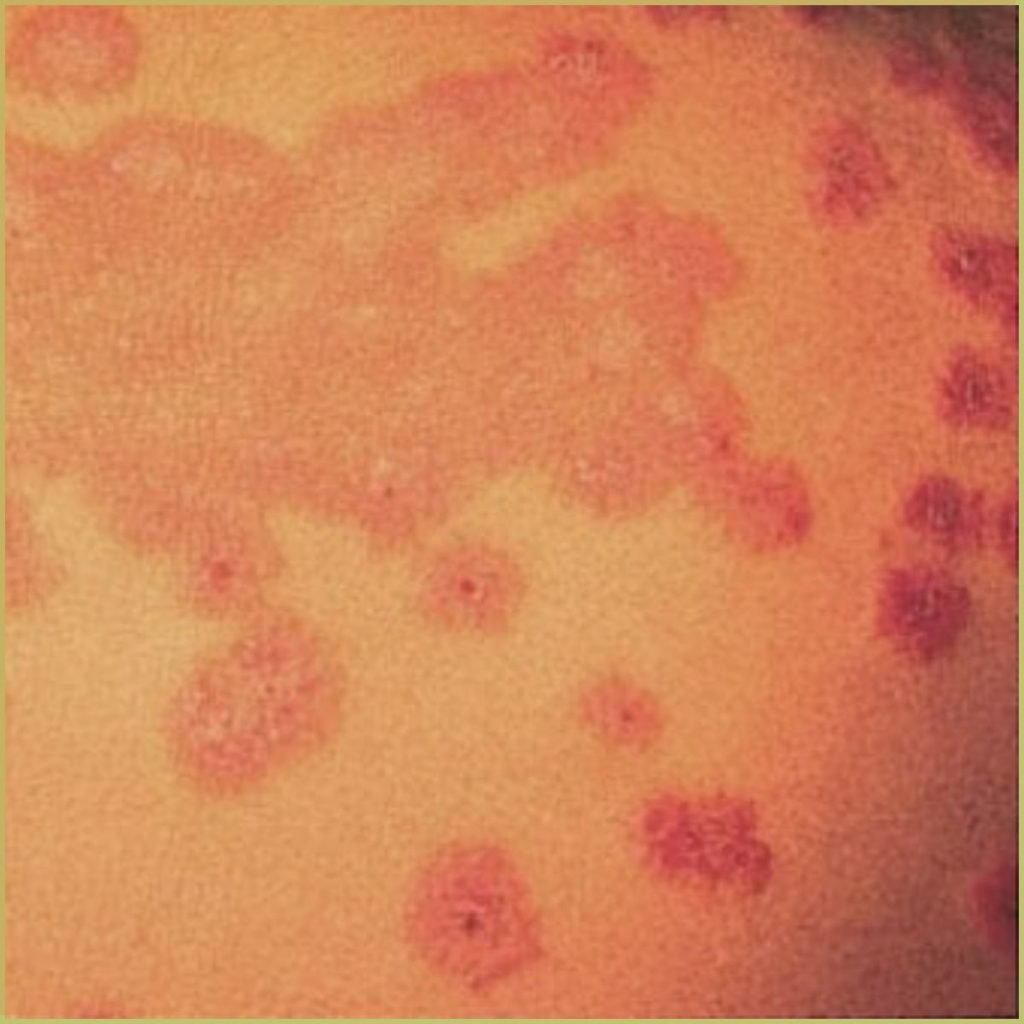

ERYTHEMA MULTIFORME

Erythema Multiforme is an cell-mediated auto-immune disorder, possibly caused by the deposition of immune complexes in the superficial layers of the skin and mucous membranes. It has been known to be associated with certain infections (herpes simplex virus, mycoplasma pneumoniae, cytomegalovirus, Epstein-Barr virus, influenza virus), a wide variety of medications (antibiotics, antiepileptics, non-steroidal anti-inflammatory drugs, statins, vaccines) and other medical conditions (inflammatory bowel disease, malignancy, menstruation). Erythema multiforme can be confused with the more serious Stevens-Johnson syndrome. The common clinical presentation includes:

- Target-like lesions (may be called iris lesions).

- Pink or red papules which can become plaques.

- Lesions on the hands, feet, arms and legs are common. Trunk less so.

- Early mucosal lesions are macular, erythematous, and occasionally bullous.

- Genital and ocular lesions may be present.

- Symptomatic, usually burning or itching. Itching can be very severe.

Diagnosis is usually based on the lesion history and clinical presentation only. If a biopsy is necessary, microscopic findings may include:

- Bulla formation visible in conventional and electron-microscopy.

- Edema in the papillary layer.

- Dermal inflammatory infiltrates consist of lymphocytes and histiocytes.

Your differential diagnosis should include:

- Acute herpetic gingivostomatitis.

- Pemphigus vulgaris.

- Major aphthous ulcers.

- Erosive lichen planus.

- Mucous membrane pemphigoid.

Treatment varies depending on the severity, but may include:

- Identification and elimination of predisposing factor(s).

- Mild form – palliative care only.

- Severe form – systemic corticosteroids and parenteral fluid replacement.

- In the case of a viral trigger, antiviral medications.